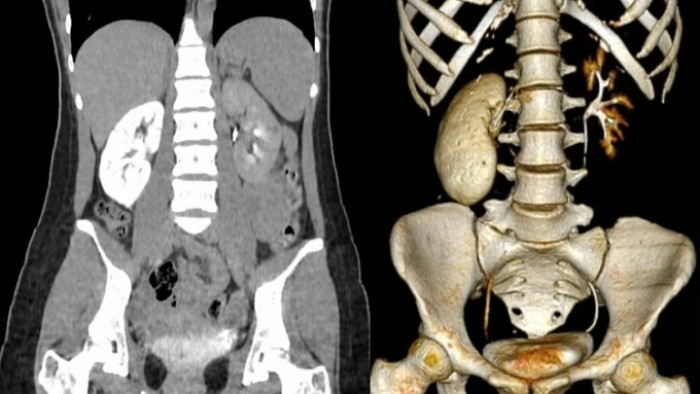

Giữa đêm, cô gái 18 tuổi phải vào cấp cứu tại Bệnh viện E trong tình trạng đau quặn vùng thắt lưng, buồn nôn, tiểu buốt. Kết quả, thận của bệnh nhân viêm nặng, gần như bị "hóa đá" do nhiều viên sỏi nhỏ gây tắc nghẽn niệu quản.

Thận bệnh nhân 18 tuổi gần như "hóa đá". (Ảnh: BSCC)